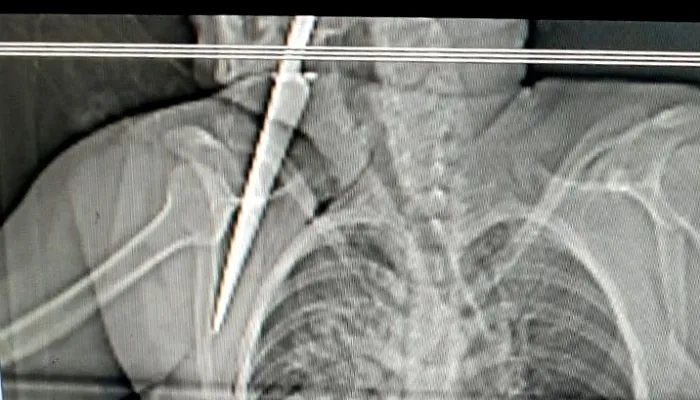

Imagem ilustrativa da imagem Homem é preso por tentar matar a ex-namorada a facadas

|  Foto: Divulgação/ PC

Um homem de 43 anos foi preso, na manhã desta quarta-feira (09), no bairro Jundiá, em Pinheiros, no Norte do Estado, após tentar matar, a facadas, a ex-namorada de 43 anos, no bairro Centro, na tarde de terça-feira (08).

De acordo com a Polícia Militar, no dia do crime, o suspeito foi até a casa da vítima e tentou reatar o relacionamento, que havia acabado há dois meses. Já que a vítima não aceitou, o suspeito começou a desferir golpes de facas no tórax da vítima, sendo que, no último golpe, a faca ficou cravada nas costas dela. O filho da vítima, de 25 anos, presenciou o crime e tentou intervir, porém foi ameaçado pelo autor.